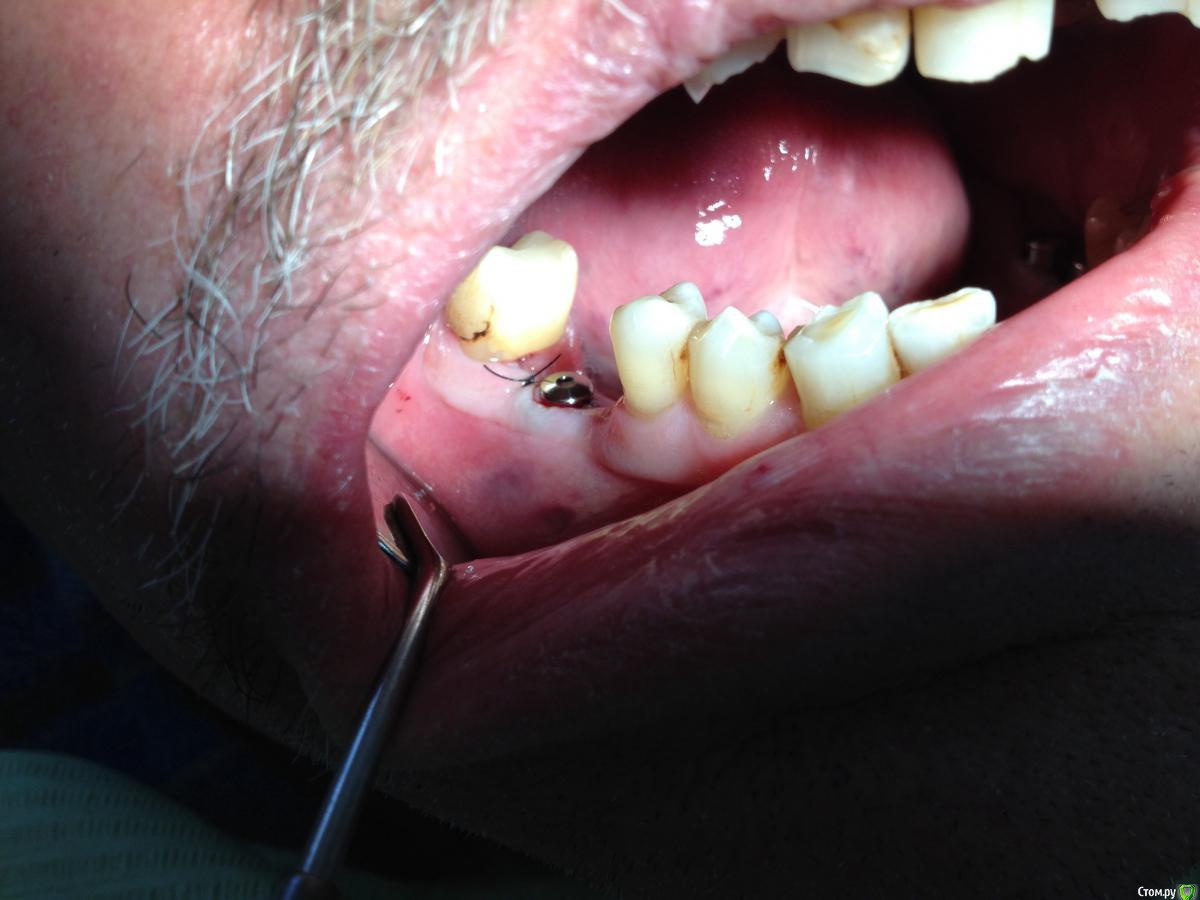

Shakirbura Опубликовано 17 октября, 2015 Автор Поделиться Опубликовано 17 октября, 2015 Наконец то увидел пациента. Парестезия сохраняется, воспаления нету, имплантат виден. Я так понимаю самое время поставить формирователь? Ссылка на комментарий

Shakirbura Опубликовано 17 октября, 2015 Автор Поделиться Опубликовано 17 октября, 2015 да, ставьте ф\дА как поставить лучше: разрез и подшить? А то там часть слизистой отмершей как сопли, вот и думаю как мне подшивать ее? Мукотома нету( Ссылка на комментарий

diesel87 Опубликовано 17 октября, 2015 Поделиться Опубликовано 17 октября, 2015 А как поставить лучше: разрез и подшить? А то там часть слизистой отмершей как сопли, вот и думаю как мне подшивать ее? Мукотома нету(Просто выкручиваете заглушку и закручиваете фдм, только сильно не усердствуйте, остальное вторичным заживет. Ссылка на комментарий

Fibez Опубликовано 17 октября, 2015 Поделиться Опубликовано 17 октября, 2015 даёшь торк 60+ на ф/д!! шутка. не больше 15. Ссылка на комментарий